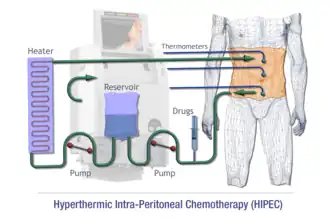

For advanced-stage patients, after cytoreductive surgery, invisible microscopic cancerous cells or nodules may still be present at the site of infection.[21] Therefore, doctors may instill a heated chemotherapy solution (≈42-43 °C) into the abdominal cavity through carters tubes for 1.5 hours.[24] Based on the principle that cancer cells normally dies at 40 °C, somatic cells remains unaffected since they die at 44 °C.[24] This novel method is proven effective with only 10% recurrence rate and no mortality recorded.[25] It is known as the hyperthermic intraperitoneal chemotherapy (HIPEC), containing docetaxel, and cisplatin.[25] Given the drug is disseminated locally in intraperitoneal regions, it has no systemic side effects on other actively reproducing cells and is preferred over systemic chemotherapy.[24]